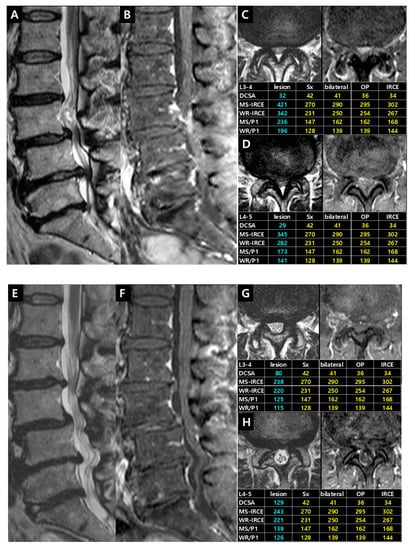

Figure 6. (A) dural cross sectional area (DCSA) on T2-weighted axial image; (B) whole rootlets IRCE (WR-IRCE, yellow color) and maximal spot rootlet IRCE (MS-IRCE, red color) on fat-suppressed enhanced T1-weighted axial image among signal intensities of manually-defined whole rootlets and each rootlet.

The quantification of IRCE was evaluated by the ratio (%) of signal intensities between the cauda equina and psoas muscle on the same axial enhanced image. The signal intensity of rootlets was measured within the manually defined region of interests (ROIs) along the boundary of the white signal by a digitizer, Maroview software (Infinitt Healthcare Co., Seoul, Korea). To define an exact margin, intrathecal rootlets were marked on the same T2-weighted axial image. The adjustment of the gray scale (window level) was necessary for the discrimination between the rootlets and cerebrospinal fluid. Manual ROI analysis was performed by superimposing previously acquired ROI on the enhanced fat-suppressed T1-weighted image (Figure 5). Two methods were composed of whole rootlets IRCE (WR-IRCE) and maximal spot rootlet IRCE (MS-IRCE) at the most stenotic level (Figure 6). WR-IRCE was obtained by recording the mean signal intensities of all outlined intrathecal rootlets. MS-IRCE was defined as the maximum value in circular ROIs (0.18 mm2) among intrathecal rootlets. In some patients, the large radiculomedullary veins showed strikingly higher signal intensities (>315) than those of other rootlets. These high signals were excluded in the subsequent measurements. The measurement of WR-IRCE and MS-IRCE on the L3–4 and L4–5 levels, respectively, were also performed in the asymptomatic control group to find a difference between such levels. The signal intensity measurement of the psoas muscle was performed within manually defined ROIs (Psoas1), which were delineated along the margin of the unilateral psoas muscle on the same enhanced axial images. In addition, circular ROIs (33.42 mm2, Psoas2) were designated within the medial portion of the psoas muscle corresponding to a mid to posterior disc space to avoid field inhomogeneity (Figure 7). Using these signal intensities, four rootlet-to-psoas ratios were defined (MS/P1 = MS-IRCE/Psoas1*100, WR/P1 = WR-IRCE/Psoas1*100, MS/P2 = MS-IRCE/Psoas2*100, WR/P2 = WR-IRCE/Psoas2*100). Those parameters were analyzed to identify the best possible candidate to stratify patients with lumbar central stenosis.